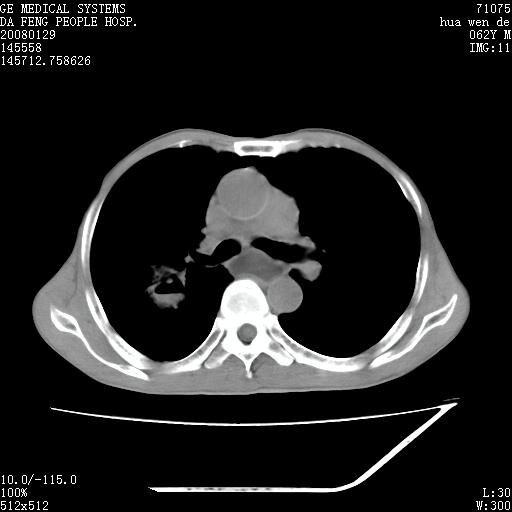

男性,67岁。作肺部检查时发现

1.整个食管扩张,未见明显占位性病变,贲门区亦未见明显占位病变,考虑:贲门失驰缓症;

2.右上肺病变边缘可见毛刺,囊壁厚度不均匀,周围境界较清楚,未见炎性渗出性影,右上肺外带可见片状影,边缘不清,考虑:肺癌伴空洞形成、右上肺炎。

15楼主分析有道理,胸腔胃除外,那么考虑贲门失驰缓症并肺部化脓感染(吸入性)可能。

肺内病灶位于右肺中叶,食道扩张后导致咽部功能受影响,吸入气管可能是存在的。

可疑之处在于:左肺未见吸入性病灶存在。另右肺癌(右肺中央型并阻塞性肺炎)不能除外

食管全程扩张,壁均匀不厚,喷门失弛缓症

右上肺空洞可见液平,临近肺野磨玻璃密度,考虑1.结核2.脓肿

贲门失驰缓症.肺部感染伴脓肿形成。支持!是否吸入性要结合临床诊断,我们影像是看不出来的。但胸腔胃能排除(1.没有手术史支持,2.双侧胸廓对称,胸壁、肋骨及胸膜规整,3,食管壁明显扩张内壁光滑,胸腔胃黏膜皱襞多较厚)。